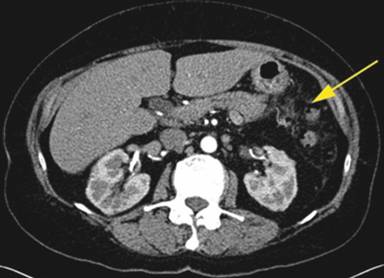

A 64-year-old Caucasian female was referred to our facility for further management of hemorrhagic pancreatitis. The patient had previously presented to an outside hospital with acute onset of severe sharp mid-abdominal pain, back pain, and nausea. She had no prior history of pancreatitis or alcohol use and had a prior cholecystectomy. Initial laboratory tests revealed a normal lipase, calcium, and triglyceride level. She had a history of hypertension, emphysema, depression, and spinal stenosis. She also had breast cancer 13 years prior, which had been treated by lumpectomy, chemotherapy, and radiation. Computed tomography (CT) scan displayed a heterogeneous fluid collection 14.3x11.2x10.0 cm and was interpreted as hemorrhagic pancreatitis involving the body and tail of the pancreas. Before admission to our hospital, she had required intensive care unit support including intravenous antibiotics and a transfusion of one unit packed red blood cells. She was started on total parenteral nutrition and took nothing by mouth. After seven days of support, she continued to have abdominal pain and was referred to our institution. Upon arrival to our facility, the patient was hemodynamically stable and afebrile. A repeat CT of the abdomen with intravenous contrast was performed at our facility 17 days after initial outside presentation (Figure 1), and it demonstrated a heterogeneous fluid collection 9.1x5.8 cm in the anterior pararenal space inferior to pancreatic tail, which likely represented a hematoma. There was also a 6 mm small pseudoaneurysm within the central portion of the fluid collection. There was no evidence of pancreatitis. An angiogram was subsequently performed and demonstrated dilatations and strictures with multiple pseudoaneurysms in the branches of the superior mesenteric artery, inferior mesenteric artery, ileal colic artery, and hepatic arteries, with one being adjacent to the pancreas (Figures 2 and 3). An attempt to embolize the pseudoaneurysm within the hematoma was unsuccessful due to tortuous mesenteric arteries. Other laboratory data obtained included C-reactive protein at 36 mg/L (reference range: 0-8.0 mg/L) and erythrocyte sedimentation rate of 72 mm/h (reference range: 0-29 mm/h). The workup for vasculitis included anti-nuclear antibodies, anti-citrullinated protein antibodies, rheumatoid factor, anti-double stranded DNA antibodies, and complement levels, all of which were within reference limits. Proteinase antibodies and myeloperoxidase antibodies were also negative. Her leukocyte count was not elevated and blood cultures were negative for growth. There was no history of congenital vascular disorders. She had no skin lesions and no renal or neurological abnormalities. A diagnosis of segmental arterial mediolysis was given based on exclusion and imaging. The patient was monitored in the hospital setting for 6 days after transfer and remained hemodynamically stable. Once abdominal pain resolved and the patient was tolerating a regular diet, she was discharged with close follow-up. A CT angiogram conducted four (Figure 4) and eleven months later (Figure 5) revealed resolution of mesenteric pseudoaneurysms and peripancreatic hematoma.

Figure 4. CT angiogram four months after hospitalization demonstrating resolution of heterogeneous fluid collection. |